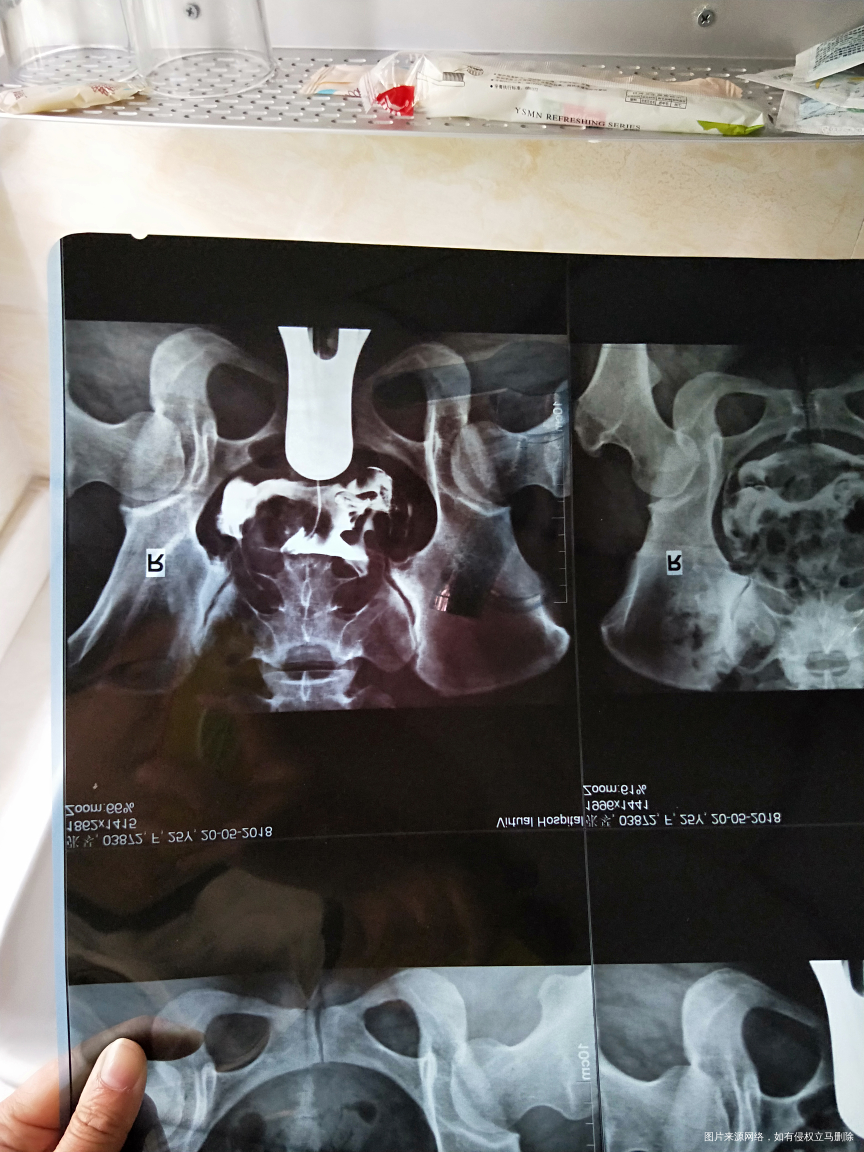

本来想去重庆妇幼保健院检查的 当时听她们说不好预约 就换了另外一家医院 不知道他们做的造影行不行 麻烦医生帮忙看看 我的情况严重吗

你好,不算严重,可以中药保守治疗,也可以介入治疗

你好,通而不畅,问题不算严重

你好,输卵管不是很通畅,可以考虑输液或者是中药保守治疗一段时间再观察。

你好,输卵管造影检查显示通而不畅,应该问题不大,可以选择中药配合理疗治疗。

你好,检查显示输卵管通而不畅,可以中药配合理疗治疗。

你好,从检查结果看是通而不畅,不算严重的,保守治疗就可以。

你好,输卵管不是很通畅,可以考虑输液或者是中药保守治疗。